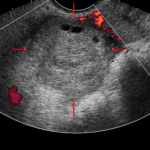

- Enlarged right ovary with peripheralization of ovarian follicles and hypoenhancement of the ovary on postcontrast images

- Ovarian torsion

Enlarged right ovary with peripheralization of ovarian follicles and hypoenhancement of the ovary on postcontrast images, concerning for ovarian torsion. Recommend urgent pelvic ultrasound for further assessment.